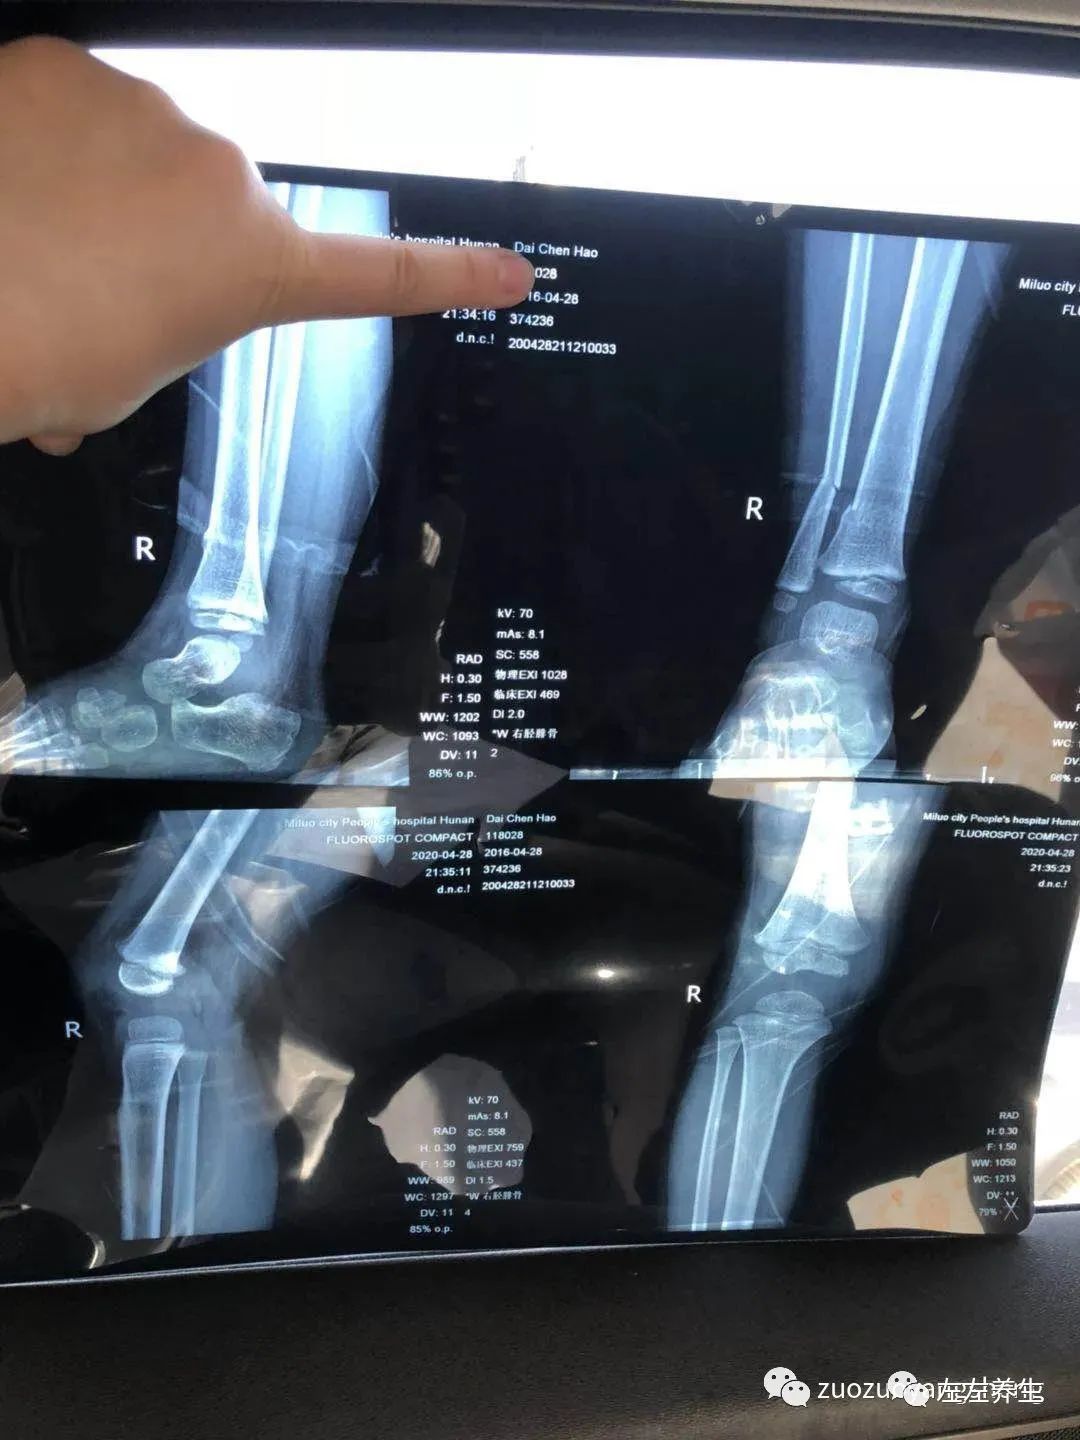

也许是感受到了我的变化,拍片子的时候他真的很乖。只是意外并不因为他的懂事而对他网开一面,结果显示右胫腓骨下端骨折、挨着的胫骨处有细微裂痕。

附骨折第一天检测单据:

附骨折第一周复查单据: